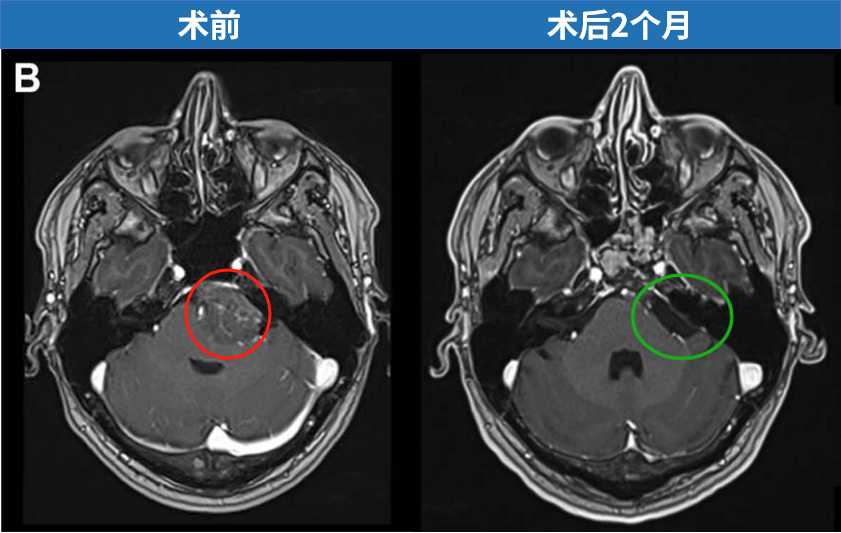

术后管理方面,患者床头抬高45度,术后第一天即开始活动,两周内避免平卧。为预防脑脊液漏,在局部麻醉下共进行了3次腰椎穿刺脑脊液引流。抗生素使用持续48小时。术后未出现神经功能缺损、脑脊液漏或感染,患者于一周后出院回家。术后一周进行了计算机断层扫描和磁共振成像检查,术后第二个月进行了第二次磁共振成像检查——两项检查均有所推迟,目的是避免成像过程中过早平卧。两次检查均证实肿瘤被完全切除。

图4. 术后2个月磁共振成像的轴位和矢状位视图,显示脑膜瘤被完全切除,脑干形态恢复正常。蝶窦被颅腔化并用腹部脂肪填充。